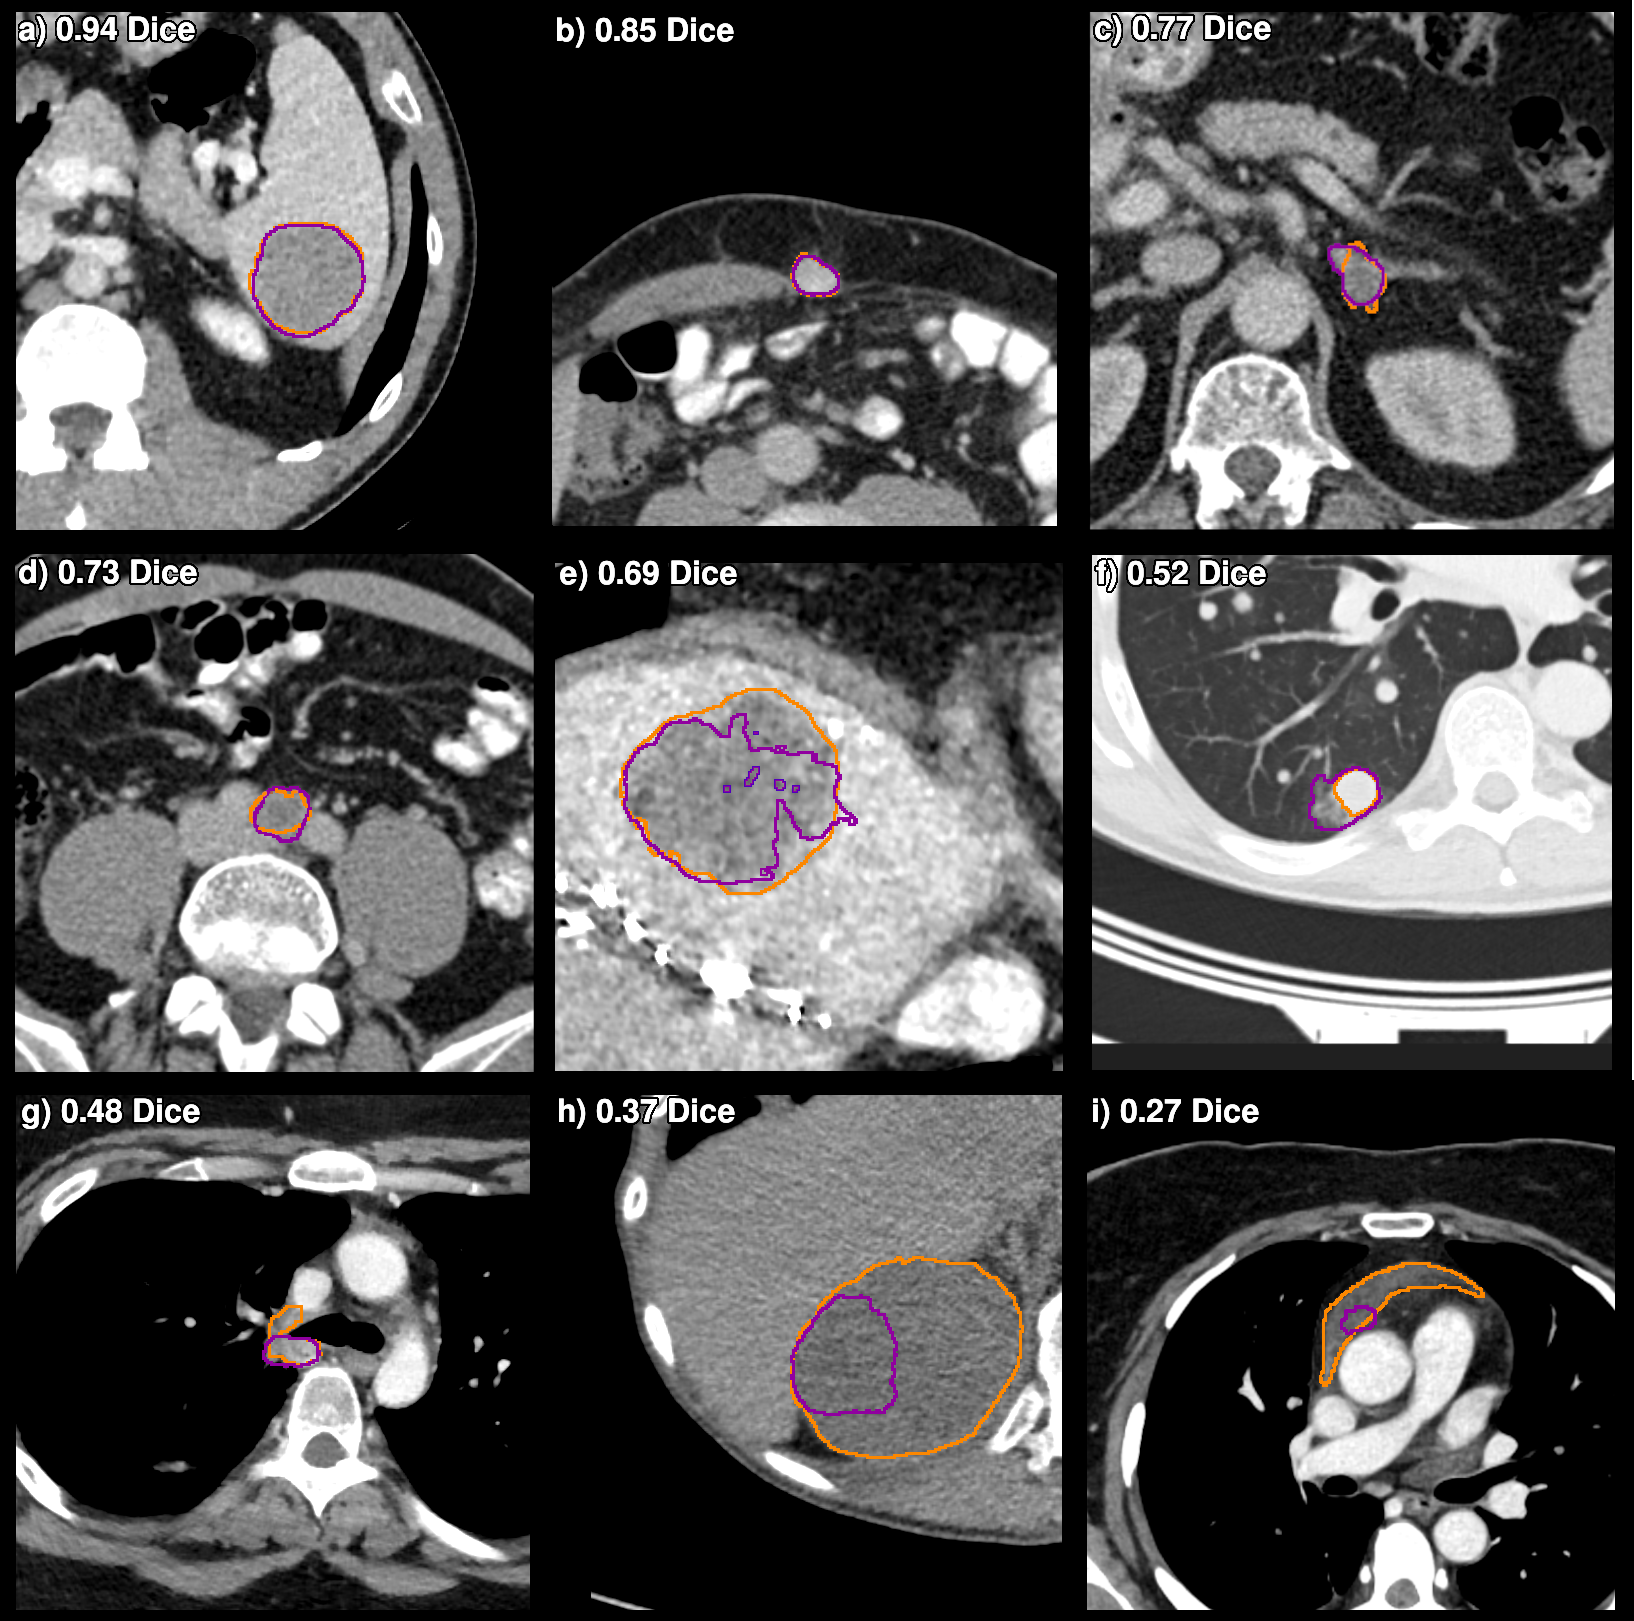

The results presented in Table 2, demonstrate considerable variations in segmentation performance across different lesion types for both models, a finding consistent with outcomes from previous segmentation challenges [22, 16]. Certain lesion types such as colon or pancreas lesions are particularly challenging due to low contrast with the surrounding healthy tissue and their irregular shapes. Figure 6 illustrates the variation in model performance across nine test cases. Lesion hhitalic_h and i𝑖iitalic_i highlight the issue of under-segmentation of larger lesions, which is a weakness of the evaluated models. One possible explanation for this is that larger lesions are less frequently observed in the training data (see Figure 1). Future work could try to address this problem by over-sampling larger lesions during training. Lesion f𝑓fitalic_f is an example of the inherent subjectivity of certain lesion boundaries, with the radiologist only segmenting the solid component of the lung lesion and the algorithm including the ground-glass area.

Refer to caption

Figure 6: Ground truth (orange line \blacksquare) and baseline model prediction (purple line \blacksquare) on axial slices from the test set. The 3D Dice score for each lesion is included in the top-left corner. The lesions visualized are: a) spleen lesion b) lesion in the abdominal wall c) adrenal lesion d) abdominal lymph node e) liver lesion f) lung lesion g) mediastinal lymph node h) kidney lesion i) Pericardial lesion. Lung lesions are visualized using Window Level: -500 HU, Window Width: 1400 HU. Lesions outside the lungs with WL: 350 WW: 40.